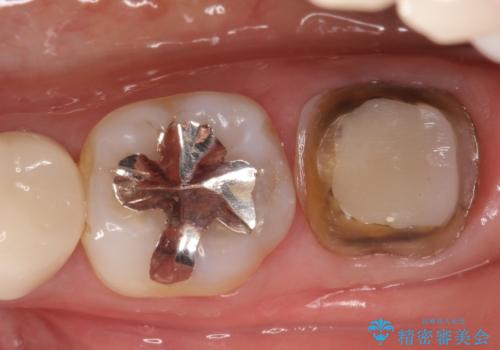

奥歯が痛い。根管治療からセラミッククラウン

- 奥歯が痛いことを主訴に来院されました。

レントゲンにて根尖病変を認め、根管治療を行ったのちセラミッククラウンにて修復しました。根管治療は川島先生に依頼。

咬合力が強くかかる部分には欠けるリスクのほとんどない金属を用いることが最良ですが審美性に劣ります。

今回は白い材料での修復を希望されたため、セラミッククラウンにて治療を行いました。